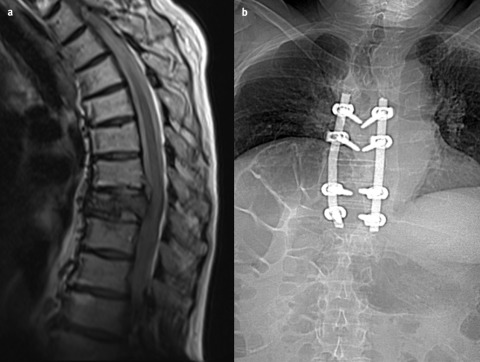

The treatment of compressive myelopathy depends on the underlying cause and the severity of symptoms. In cases of acute spinal cord compression, surgical intervention is often required to relieve pressure and prevent further neurological damage. Surgical options may include decompression laminectomy, discectomy, or tumor resection.

Traumatic spine surgery is a specialized field focused on treating injuries to the spinal column and spinal cord resulting from trauma. These injuries can arise from various causes, including vehicular accidents, falls, sports injuries, or acts of violence. The primary goal of traumatic spine surgery is to stabilize the spine, relieve pressure on the spinal cord and nerves, and restore as much function as possible. Understanding the complexities, advancements, and challenges involved in these procedures provides valuable insights into spinal trauma care.

Recent advancements in technology and surgical techniques have significantly improved outcomes in traumatic spine surgeries: